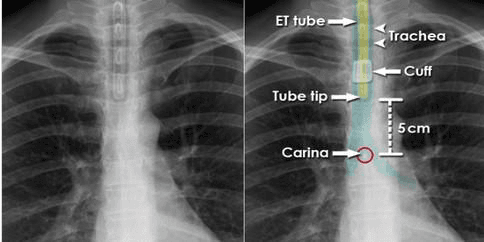

위의 영상은 정상적인 ET tube의 위치를 보여주는 사진이다. ET tube는 입을 통해 삽입되고 입에 고정되기 때문에 목이 굴곡, 신전되는 것에 따라 tube가 빠져나올 수도 있고 더 깊이 들어 갈 수 도 있다. 그래서 위의 영상과 같이 목이 신전 또는 굴곡되지 않은 상태에서 ET tube의 끝이 carina로 부터 5~7cm 떨어진 곳에 위치 해야한다.